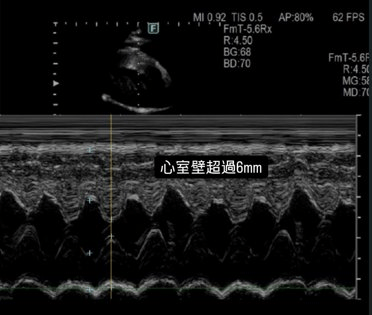

| 心臟超音波 | 心臟檢查的黃金標準。清晰觀察心臟結構、瓣膜開合、血流速度與收縮/舒張功能。 | 結構與功能 |

萌寵引進最新日本富士原廠人醫頂級超音波。其影像精確度比擬 CT 掃描,能提供高解析度的心臟結構畫面,大幅減少因影像不清晰而拉長檢查時間的問題。